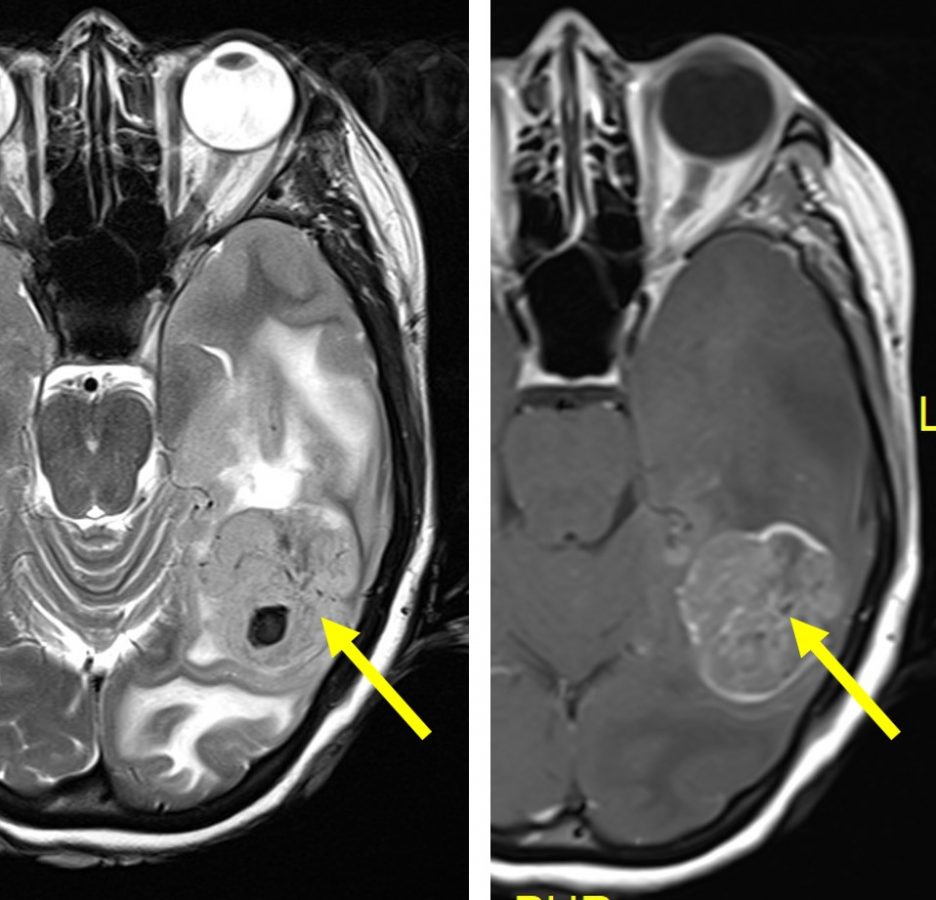

- Rezonans magnetyczny (MRI) – MRI jest uważany za najlepszą metodę obrazowania mózgu przy diagnozowaniu glejaków mózgu. Polega na wykorzystaniu pola magnetycznego do uzyskania bardzo szczegółowych obrazów mózgu, które mogą pomóc w identyfikacji ewentualnych guzów lub nieprawidłowości w tkance mózgowej.

- Tomografia komputerowa (CT) – CT, podobnie jak MRI, może dostarczyć obrazów mózgu, lecz jest on mniej szczegółowy, i często wykorzystywany jest jako uzupełnienie MRI.

- Biopsja mózgu – jeśli istnieje podejrzenie glejaka mózgu, lekarz może zdecydować o pobraniu próbki tkanki za pomocą biopsji mózgu. Próbkę można następnie ocenić pod mikroskopem, aby potwierdzić rozpoznanie.